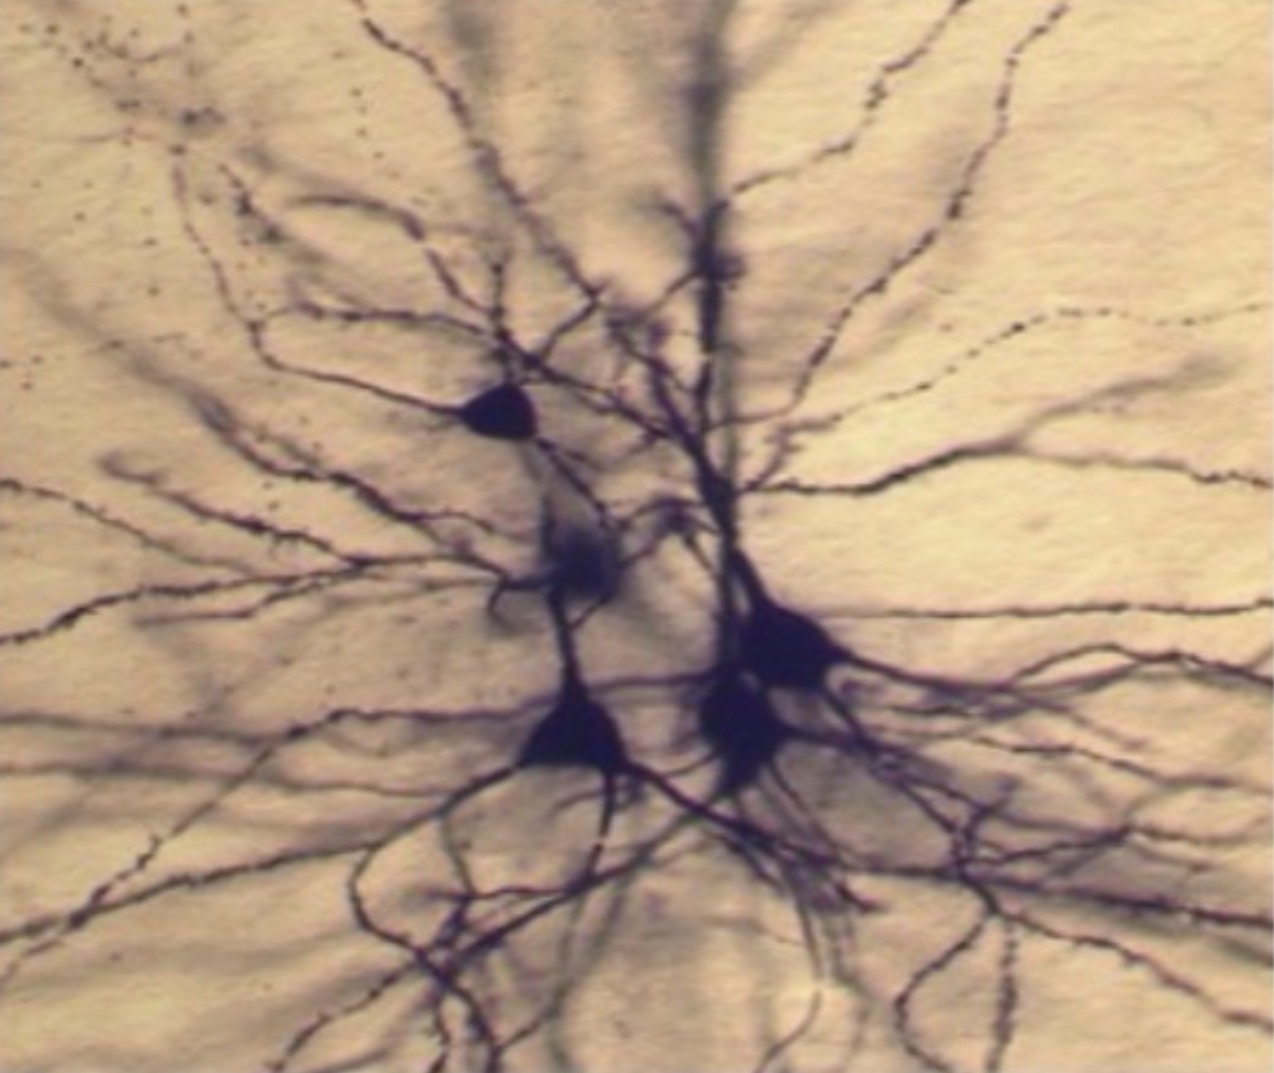

What is this

Hippocampal pyramidal cells

several pyramidal neuron